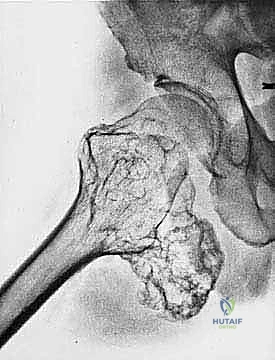

3. الكسور المرضية: حدوث كسر في العظم نتيجة إصابة طفيفة جداً لا تسبب كسراً في العظم السليم.

| حدود الورم في الأشعة | واضحة، محددة بدقة (Sclerotic margin) | غير واضحة، متآكلة (Moth-eaten appearance) |

| اختراق قشرة العظم | نادر جداً | شائع جداً، يمتد للأنسجة الرخوة المحيطة |

| الانتشار (النقائل) | لا تنتشر لأعضاء أخرى | تنتشر غالباً إلى الرئتين أو عظام أخرى |